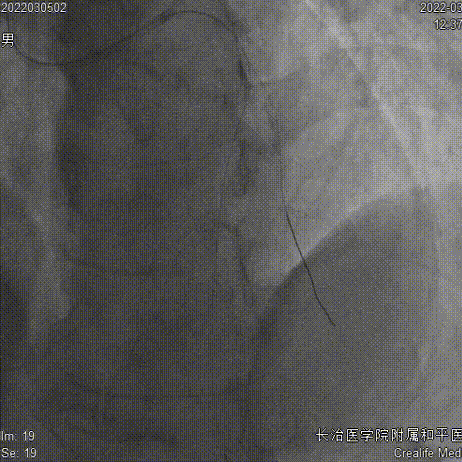

药物球囊2.75x35mm、Telescope™导引延长导管

药物球囊定位、释放

对于病变迂曲、钙化的情况使用Telescope™导引延长导管增加药物球囊通过性,减少输送时的药物丢失。